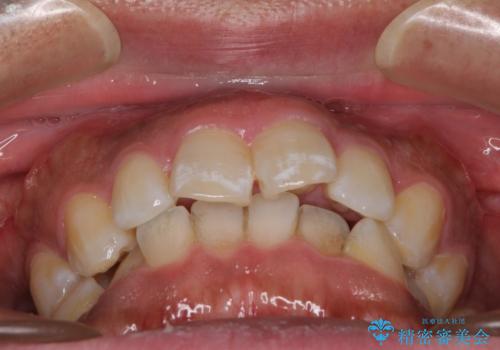

- 上下前歯部の叢生を気にして来院された患者様です。

レントゲン撮影により、右上奥歯が折れていることが分かりました。

患者様自身も何となく違和感を覚えていたとのことで、インプラント補綴治療を行うこととしました。

歯列不正は比較的軽微であったので、インビザラインによる矯正治療とし、矯正治療中にタイミングを見て抜歯とインプラント埋入を行う予定としました。